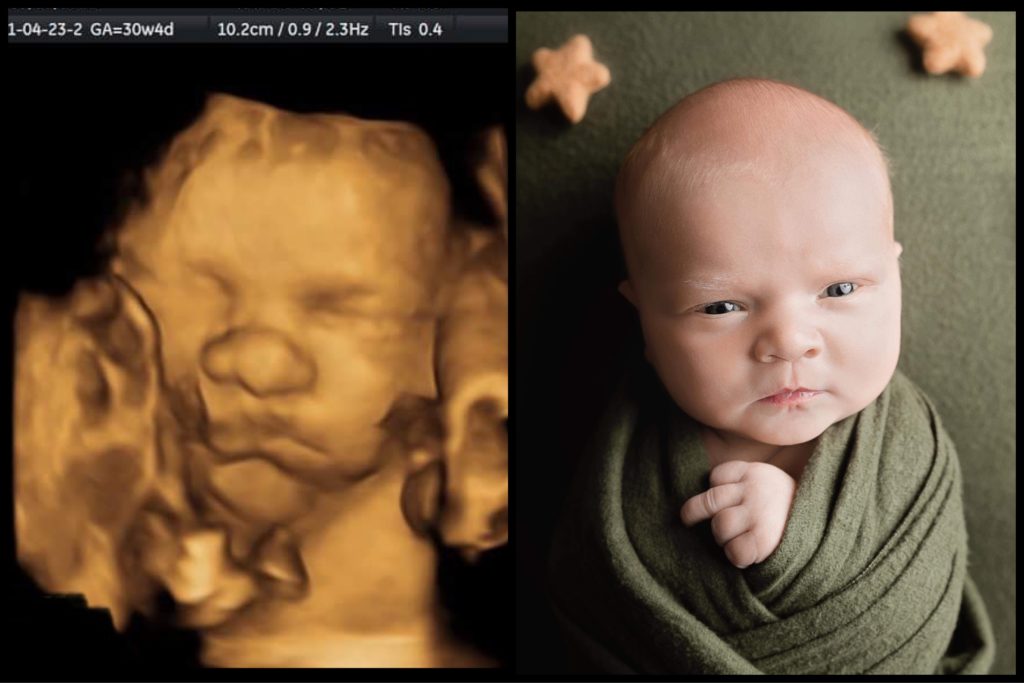

Imagen de un centro de ultrasonido Miracle 4D

¿Qué es el ultrasonido 3D/4D? El ultrasonido es una tecnología que ha estado en uso durante más de 40 años. Utiliza ondas de sonido que son traducidas por una computadora en imágenes. Se coloca una sonda en el vientre cubierta con un gel que disminuye la resistencia a las ondas sonoras reflejadas. La ecografía 2DSigue leyendo «Imagen de un centro de ultrasonido Miracle 4D»